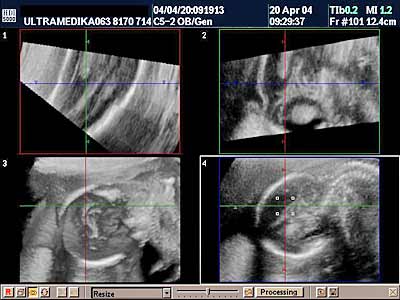

Ultrazvučni skrining baziran, na osobini lica i dužini prsta u ranom II trimestru

U medicinskom časopisu „Ultrasound in Obstretics & Gynecology“ iz marta meseca ove godine, kolege iz Izraela i Engleske uradili su zajedničku studiju nakon koje su izložili sledeće rezultate.

Zahvaljujući uznapredovaloj ultrazvučnoj dijagnostici gde sonde visoke rezolucije omogoćavaju dijagnozu u toku trudnoće na osnovu otkrivanja ovih finih i skrivenih anomalija ploda sa Down -im sindromom (DSy) .

U I trimestru u najevećem broju slučajeva kao i u ranom II trimestru ( 12-16 nedelja gestacije, 3-4 mesec) se već duže prati izsostanak formiranja jedne ili obe nazalne kosti ili njihova manja dimenzija. U toku 2005 i 2006 godine uočeno je da loš elasticitet kože kod ovih plodova sa DSy se vidi kao povećano prenosno zadebljanje kože (PT). Zadnjih nekoliko godina takodje je uočeno da su svih pet prstiju šake manji kod dece sa DSy nego kod dece bez hromozomske anom alije.

Postoji nekoliko preduslova da se ovi markeri uoče:

1. Ugao ulaznog ultrazvučnog talasa i osovine kostiju nosa ploda moraju zauzimati ugao od 45 stepeni da ne bi došlo do lažnog skraćenja ili odsustva nosnih kostiju (NB).

2. Anehogena rskavica izmedju frontalne (čeone) kosti i ehogene kosti nosa takodje omogućava tačno prepoznavanje nosnog grebena.

3. Prenazalna debljina kože –PT se meri izmedju frontonazalnog ugla i spoljne konture kože.

4. Da bi se ovi markeri uočili aparat mora posedovati HD ZOOM (uvećanje slike bez smanjenja njenog kvaliteta) soobzirom da izmeren strukture iznose samo nekoliko mm.

5. Najčešće se meri 2 ili 3 prst jer su oni najčešće ispravljeni, pri čemu se u obzir mora uzeti i meko tkivo prsta. Od ranije se zna da ušiljavanje zadnje falange prsta (klinodaktilija ) kao i odsustvo medijalne kosti petog prsta tj. njegovog ukupnog skraćenja takodje predstavljaju markere za DSy.

Ovi ultrazvučni markeri su prisutni u ranom II trimestru (16gn). Medjutim ako postoje linearne sonde od 12 MHz moguće je ove markere uočiti i u I trimestru.

Zbog različite veličine ovih struktura u zavisnosti od starosti trudnoće uobzir se uzimaju odnosi PT/N kao i odnos dužine prasta sa širinom šake.

Senzitivnost ovih markera je oko 76% uz 6,7% lažnog pozitivnog nalaza.

Zaključak

Ultrazvučni skrining za otkrivanje DSy, ako ne uzmemo u obzir urodjene srčane mane, zasnovan je najvećim delom na skrivenim osobinama ovih plodova a mnogo manje na nisko usadjenim ušima. Bez obzira što je broj „soft „ markera veliki i procena ploda na osnovu osobina fenotipa, takodje poveća ukupnu senzitivnost u otkrivanju plodova sa DSy. Ovo ima smisla soobzirom da kada se postignu optimalni uslovi za merenje nosnih kostiju dodatno vreme za merenje prenazalne debljine kože –PT ploda nezahteva bitno povećanje vremena ultrazvučnog pregleda trudnoće.